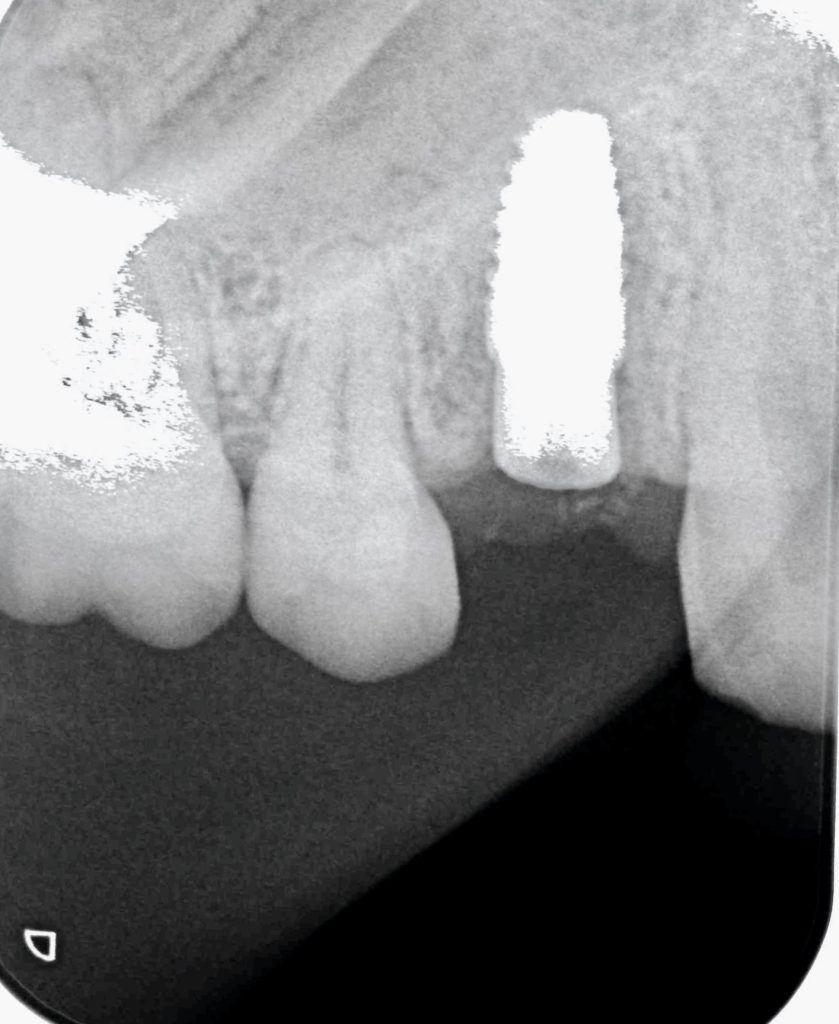

神経が無く、症状を感じにくい状態ですが、歯根内部に吸収があり、いわゆる穴が空いていました。(専門的には外部吸収と言います)

抜歯と同時にインプラントを埋入し、3ヶ月後に被せ物をセットできると思います。